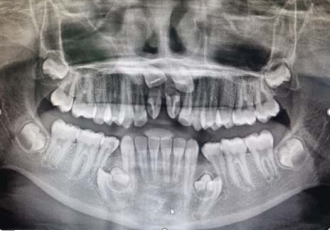

Uma criança de 11 anos de idade, 32 kg, apresenta queixa de demora de erupção dos incisivos permanentes superiores. Observe o aspecto clínico e radiográfico do caso descrito e julgue os itens a seguir.